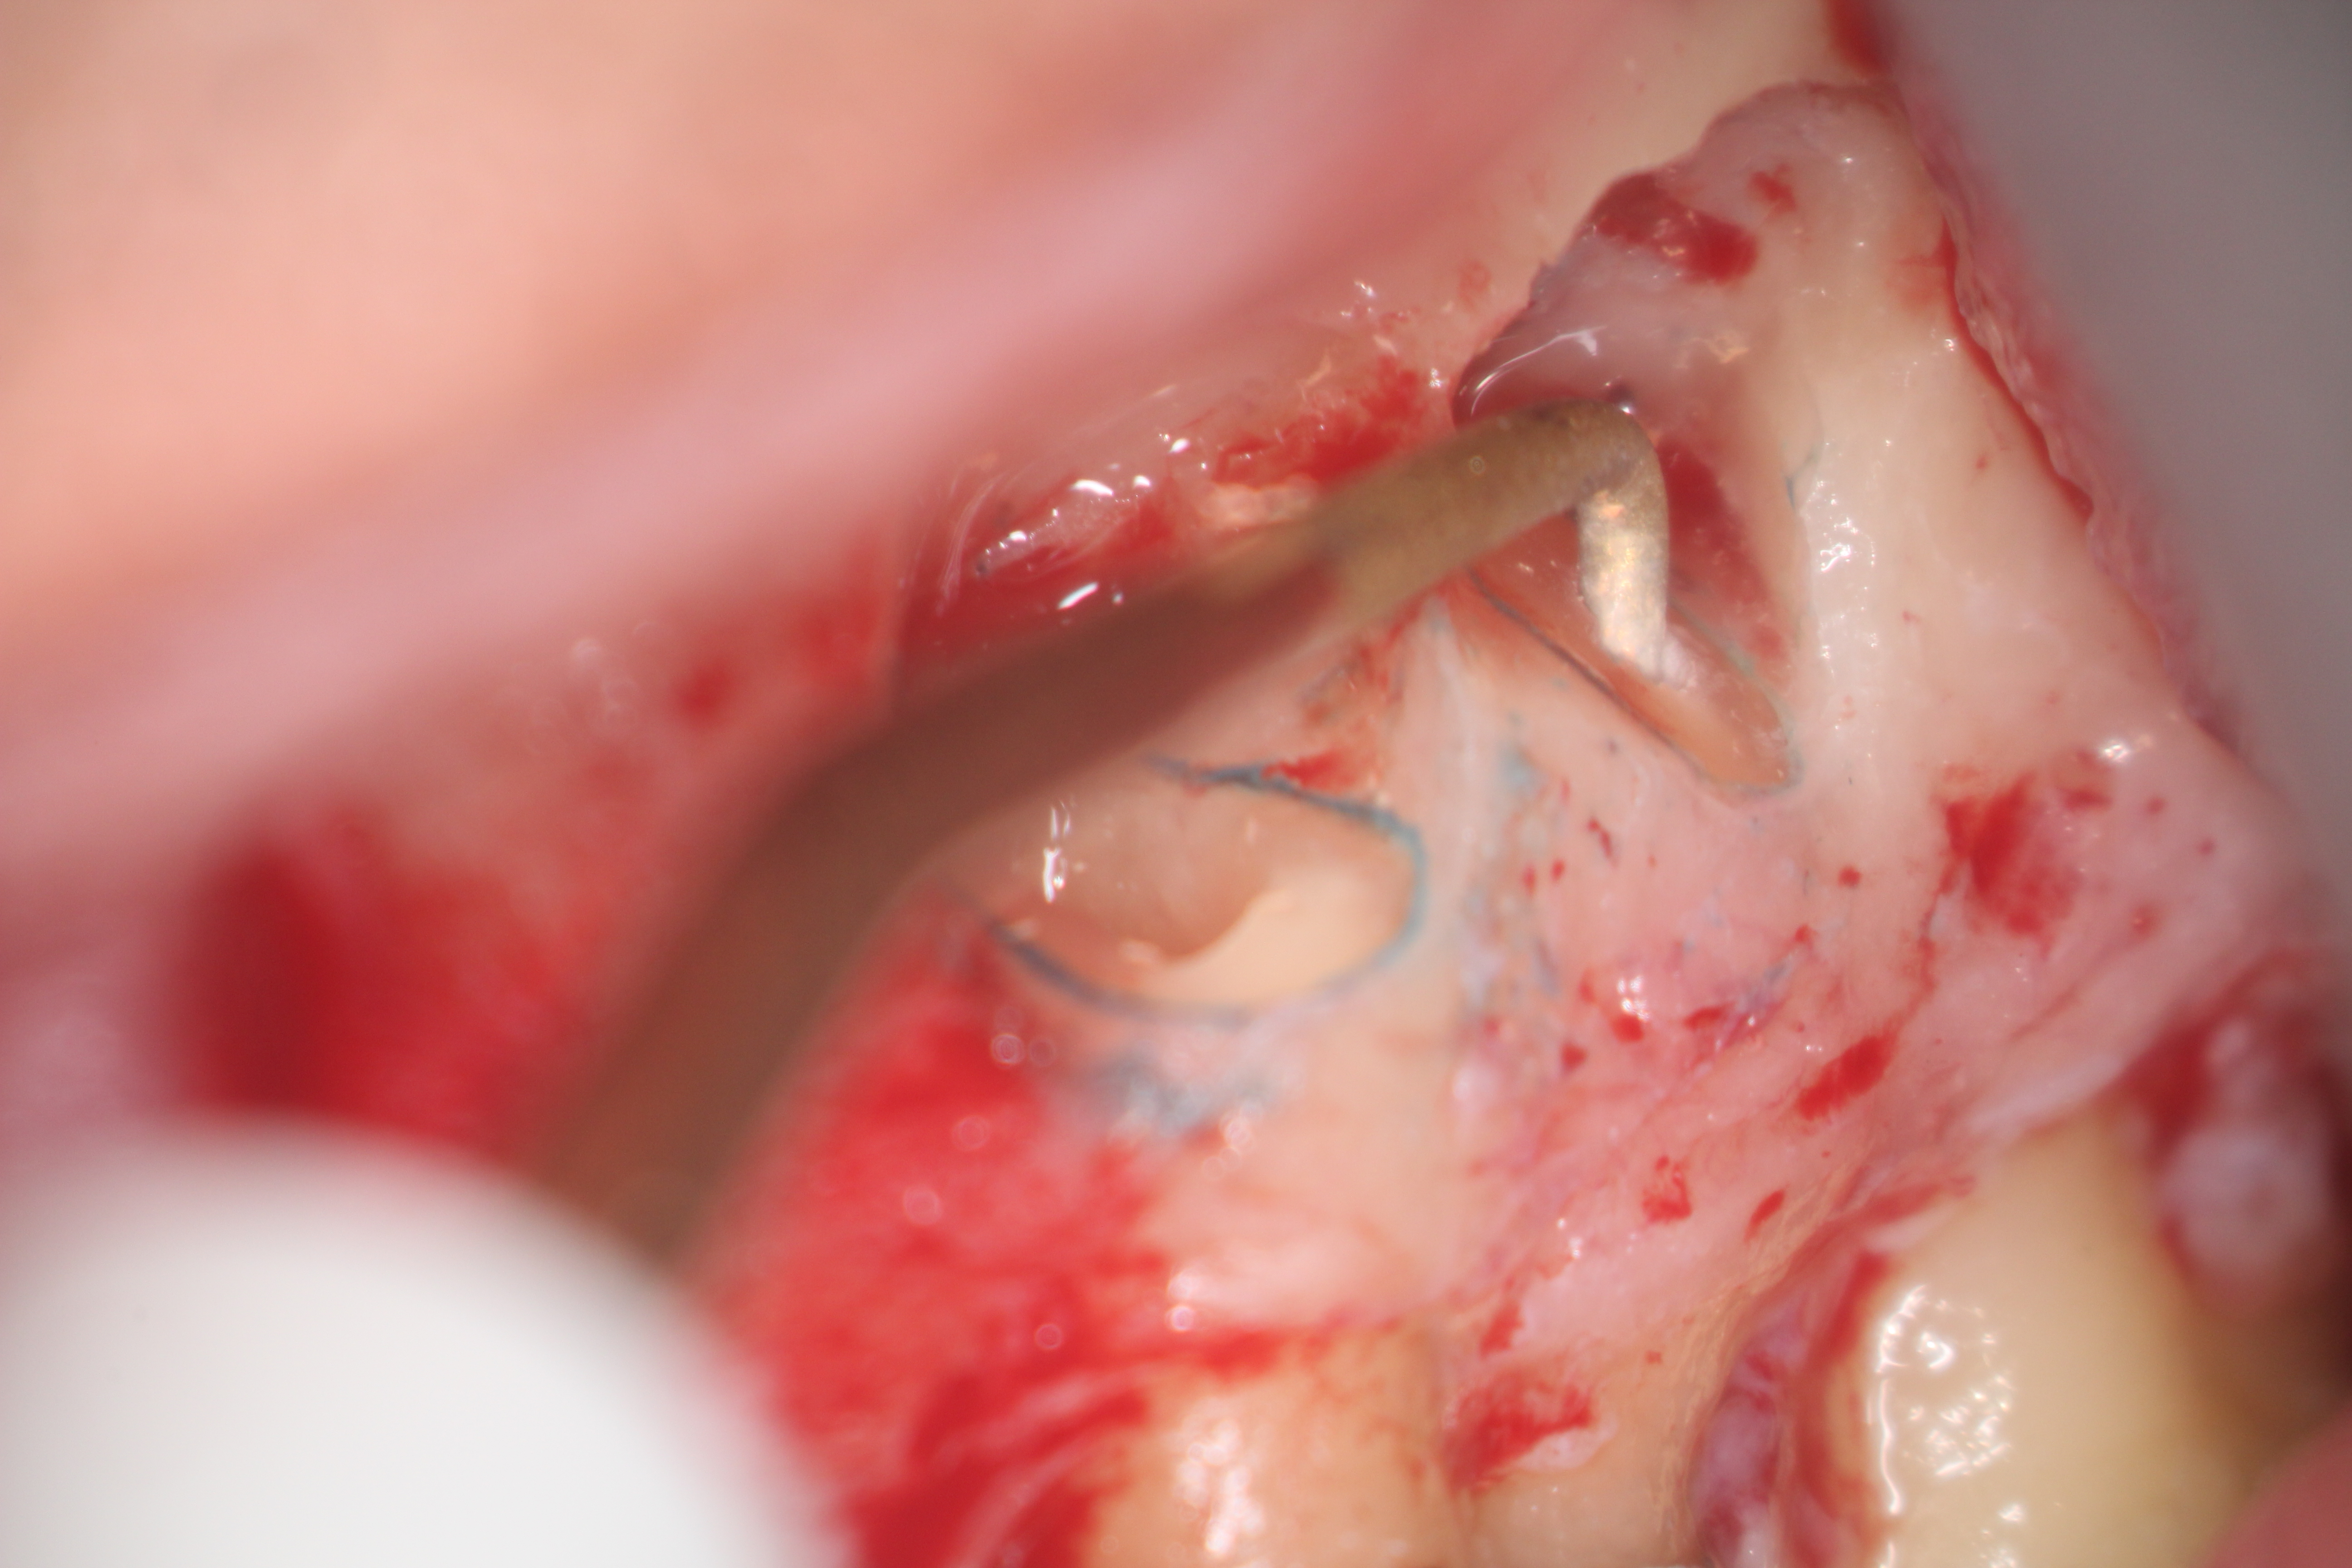

Fig 16. 3-mm root resection with methylene blue staining.

Figure 16

Clinical procedure: In the case of a root-end filling (Figure 15), once the apical 3 mm of the root has been resected (Figure 16) the canal system is then opened and cleaned with surgical ultrasonic tips to create the retro-preparation (Figure 17). After this is completed, the retro-preparation is dried and MTA is then placed and condensed in that space creating the retro-filling (Figure 18 through Figure 20).